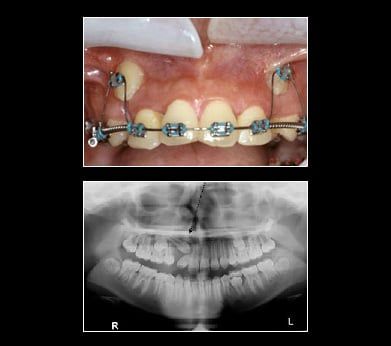

Treatment for Impacted Canines

After assessing your situation, InfoStar Dental Template 1 will devise a plan to make room for your canines. With a typical oral surgery and the assistance of an orthodontist your canine will find their way into their proper place over time.